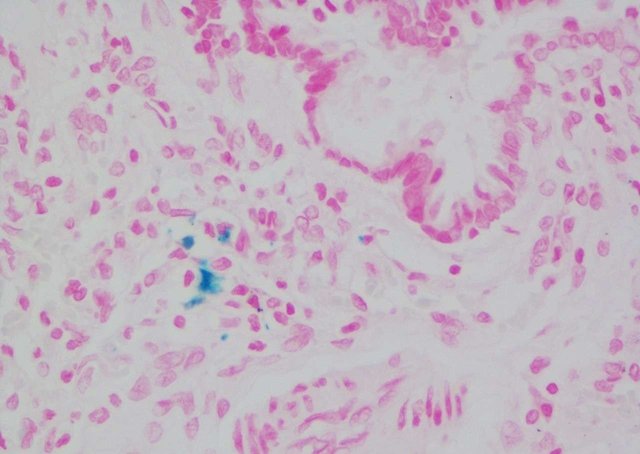

铁离子呈蓝色;细胞核呈红色。

普鲁士蓝染色样片参考: